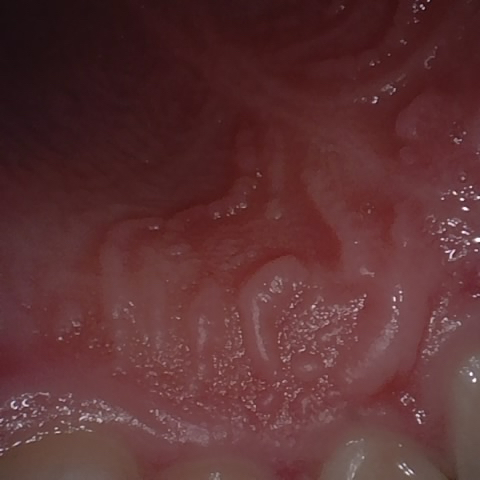

Annotated as "Good"